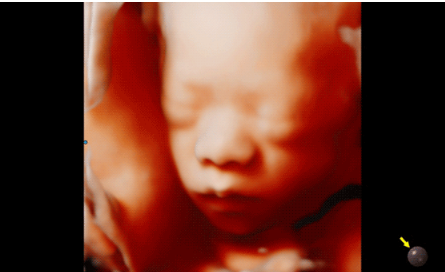

Hera i 10繼承并升級了全球首款5D超聲“三星麥迪遜WS80A”的“晶體結構”成像理念,即將CrystalBeam?波束形成技術、CrystalLive?超聲成像引擎、S-Vue Transducer?視覺傳感器集于一身,提供更清晰的圖像。

3D/4D成像方面,Hera i 10通過結合先進的圖像渲染技術,著重加強了邊緣和小結構的可視化能力。